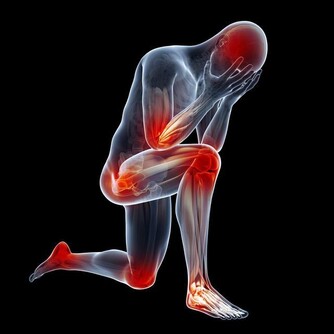

① 肝臟受損。喝酒過度,容易使脂肪堆積在肝臟,損傷肝細胞,甚至誘發脂肪肝。

② 胃潰瘍。酗酒還會嚴重刺激胃部,容易造成胃出血,威脅生命安全。

③ 中樞神經受損。酒精還會使神經系統受到損壞,表現出記憶力下降、精神異常等現象。

④ 猝死。過量飲酒,還可能會抑制腦部呼吸中樞,導致呼吸停止;同時降低血糖,引起猝死。